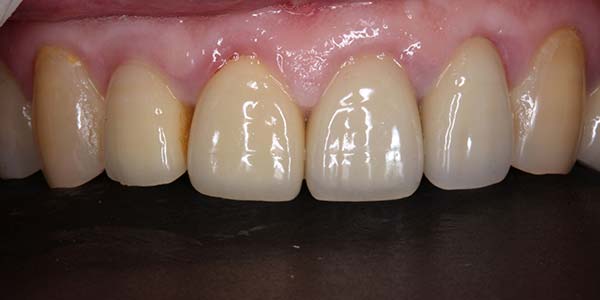

"4個月骨整合完成後,利用植牙支台齒,製作全瓷冠,恢復外觀"

裝戴正式假牙

8年追蹤

After